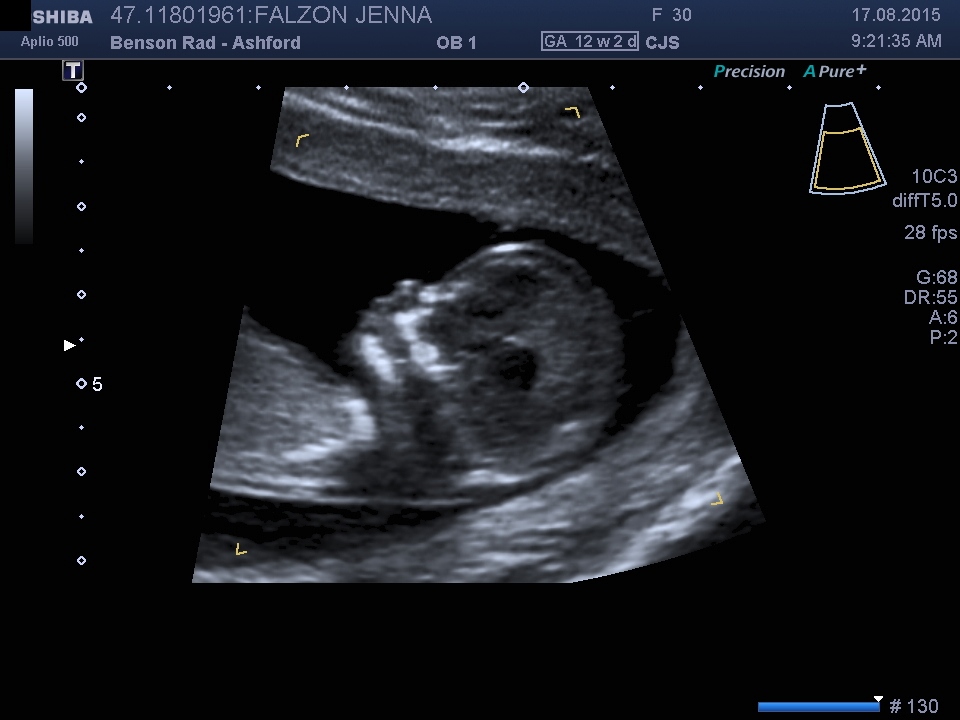

any guesses in the gender from 12 week scan?

Its too early for potty shots. Just for fun I'll say the face and head shape look girly!

Maybe girl? Do you have any profile shots showing the entire baby?

I though head looked girly too :)

Maybe girl. Without profile shot of the nub, it's hard to say.

Girl lean

Girl